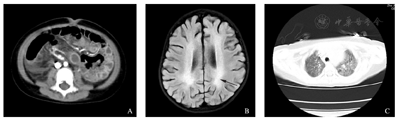

A.腹部增强CT示肠管形态僵硬,肠壁不均匀强化,肠壁增厚,肠间隙模糊;B.患儿头颅磁共振示大脑半球深部脑白质FLAIR序列呈高信号;C.胸部CT肺窗示肺野内散在密度增高影。

病例1,患儿,女,3岁1个月,因"发热、咳嗽5 d,腹泻4 d,全身水肿1 d"于2020年8月29日入院。既往体健。入院查体:T 38.4 ℃,P 160次/min,R 48次/min,BP 92/61 mmHg(1 mmHg=0.133 kPa),SpO2 100%。神志清,精神欠佳,颈软,颜面部及双手足水肿,咽充血,呼吸促,可见吸气性三凹征,双肺呼吸音粗,未闻及干湿性啰音,心律齐,心前区未闻及病理性杂音,腹平软,肝肋下3 cm,脾肋下未及肿大,神经系统查体无异常,全身无皮疹,指趾端未见脱皮,口唇无皲裂,未见杨梅舌,双眼结膜无充血,肛周皮肤红肿,有破损,卡疤不红。患儿入院后出现血压低,心脏超声提示心包积液,心肌酶增高明显,心包积液及外周血高通量检测示HHV-6B阳性,诊断为病毒性心肌炎,予阿昔洛韦抗病毒治疗及营养心肌后,患儿心包积液减少,血压正常,查心脏超声提示心功能正常。入院当天患儿出现腹胀腹痛伴反复腹泻及血便,查肠道病毒阴性,腹部增强CT提示肠管形态僵硬,肠壁不均匀强化,肠壁增厚,肠间隙模糊(图1A),考虑坏死性小肠结肠炎,予抗感染及对症支持保守治疗后,患儿腹胀及血便情况好转,表现为排黄稀便,偶可见血丝,偶有腹胀,排便排气后好转,未再诉明显腹痛。患儿入院后亦出现神经系统异常表现,主要表现为神志淡漠,头颅MRI提示大脑半球深部脑白质内大片状异常信号(图1B);脑电图示异常儿童脑电图:多量持续性、广泛性δ活动,两枕区尤著;查脑脊液常规及生化正常,考虑病毒性脑炎,予继续阿昔洛韦抗病毒及加用小剂量甲泼尼龙后,患儿神志转清,神经系统无阳性体征。患儿胸部CT提示肺炎(图1C),予抗感染治疗后好转。患儿住院期间予查CD19波动于4.1%~8.95%,全外显子基因检测未发现异常;后患儿病情稳定,于9月25日出院至康复医院行康复治疗。出院后19 d患儿再次因"呕吐8 d,发热伴全身水肿1 d"于10月14日转回我院治疗,入院查体:T 38.4 ℃,P 186次/min,R 32次/min,BP 80/55 mmHg,SpO2 99%。神志清,精神欠佳,颈软,咽充血,呼吸促,可见吸气性三凹征,双肺呼吸音粗,未闻及干湿性啰音,心律齐,心前区未闻及病理性杂音,腹软,腹膨隆,脐周压痛,肝肋下2 cm,脾肋下未及肿大,神经系统检查未见阳性体征,全身无皮疹,毛细血管充盈时间2 s。入科当晚患儿出现反复的血压伴心率下降,腹部膨隆进行性加重,结合患儿上次住院情况,考虑患儿存在肠坏死,完善术前准备,立即联系普外科会诊行手术治疗,但患儿予大剂量血管活性药物应用下血压仍无法维持,凝血功能极差,迅速出现肺出血及严重的电解质紊乱,最终无法进行手术,抢救无效宣告死亡。